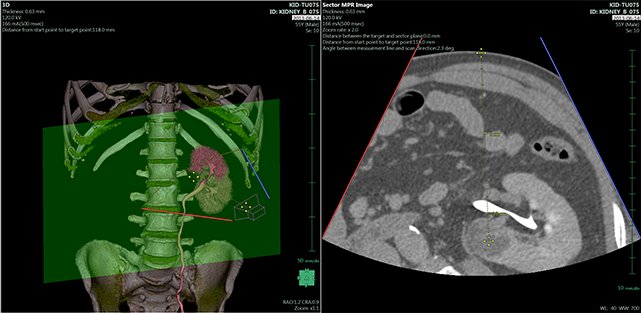

ANYTHINK 经导管主动脉瓣膜置换术分析系统